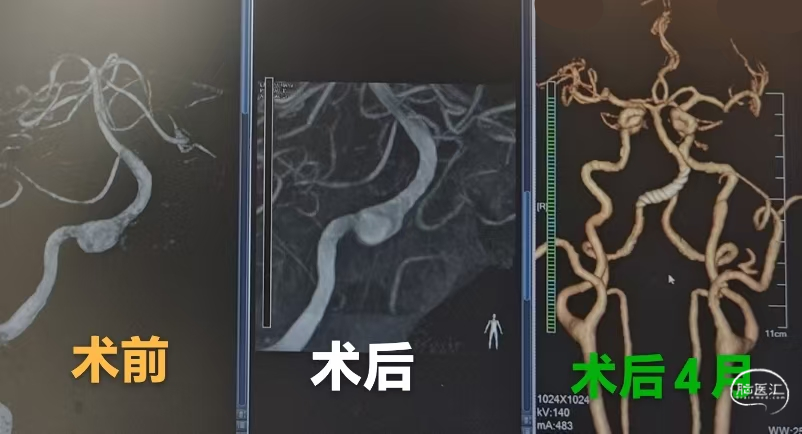

术前3D影像:

DSA正侧位造影显示:右侧椎动脉V4段夹层动脉,瘤颈约8mm,血管直径约3.5mm。

术后造影:

术后造影显示,囊内有明显的滞留、远端血流通畅。

患者治疗后4个月复查,3D成像清晰可见支架贴壁良好,载瘤动脉未见狭窄、夹层病变血管修复良好。

患者4个月随访可见,夹层病变血管修复良好、未见管腔狭窄及动脉瘤复发等影像,达到了很好的预期疗效。